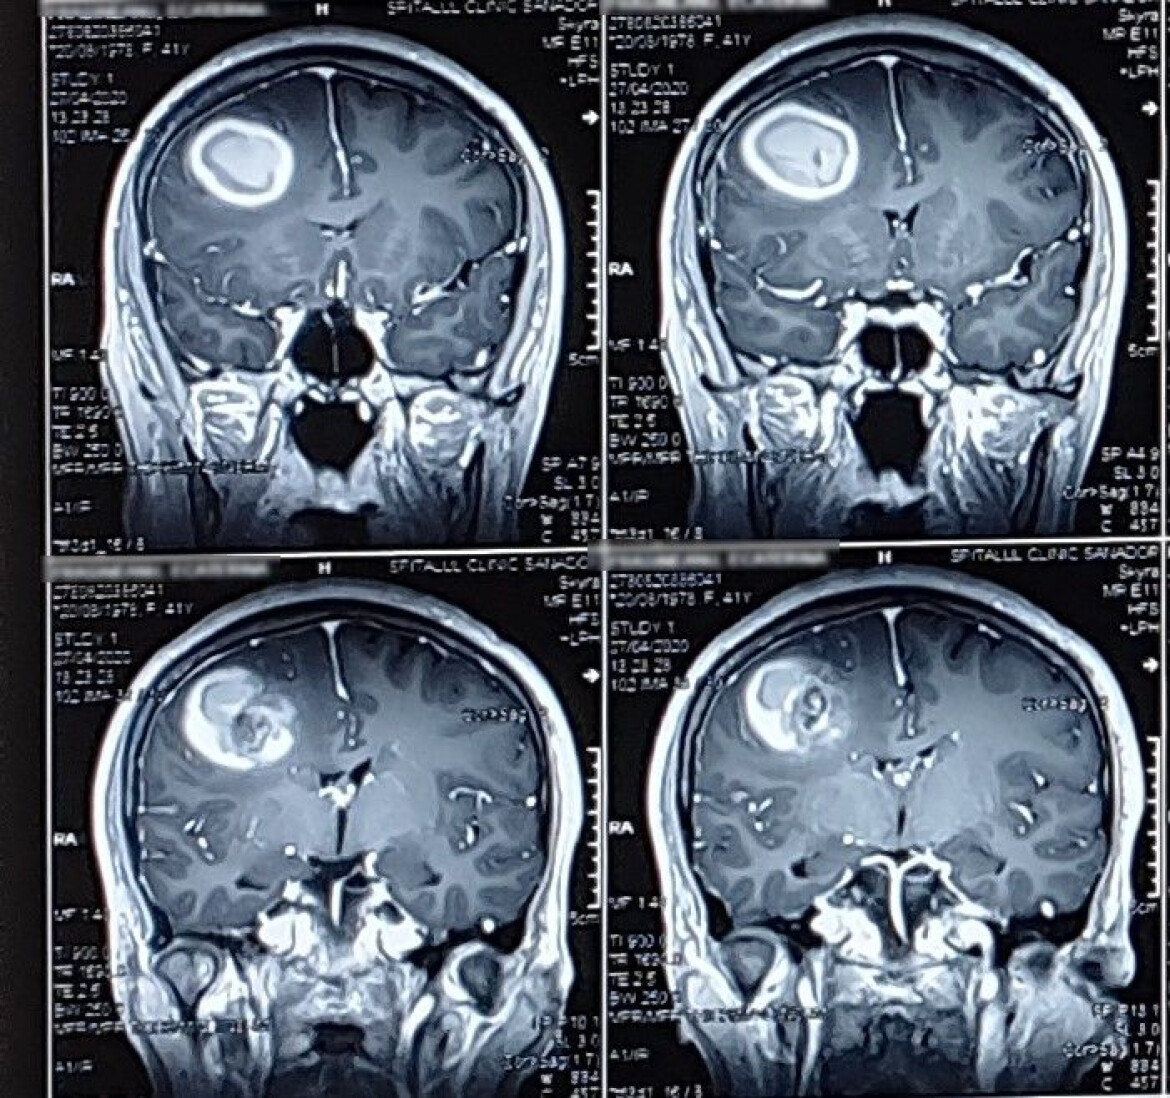

„Am fost foarte incantata de bunele practici, de amabilitatea personalului sanitar si de profesionalismul echipei de medici neurochirugi, condusa de reputatul profesor univ. dr. ALEXANDRU VLAD CIUREA, in cazul operatiei de cavernom frontal voluminos, cu hematom, realizata microchirurgical si ghidata de neuronavigatie craniana, la sfarsitul lunii aprilie 2020. Operatia a fost realizata cu succes, a fost confortabila pentru mine si apartinatorul meu, din toate punctele de vedere si, dupa 5 zile de la aceasta, am putut sa fiu iarasi eu, cea care fusesem inainte, un om vesel, optimist, independent in controlul motricitatii, 100% activa/apta din punct de vedere intelectual.